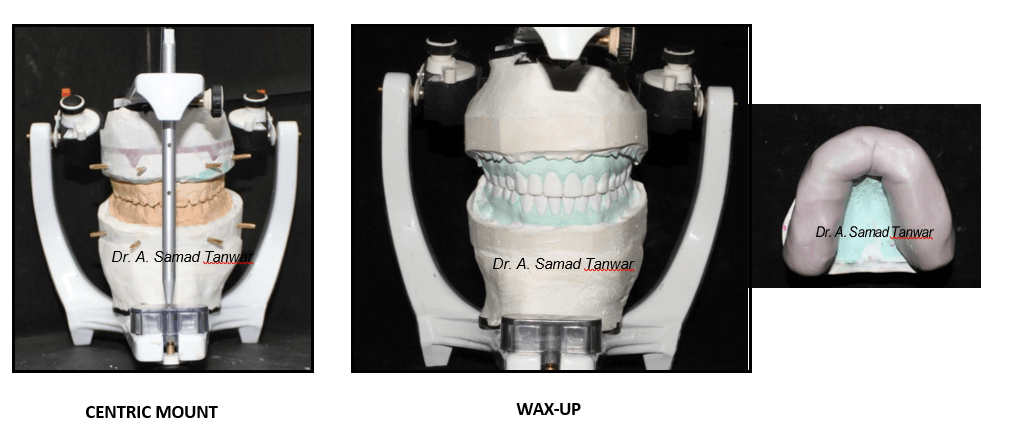

The patient was guided into centric relation and it was mounted on a semi- adjustable

The articulator was programmed using protrusive and lateral interocclusal

Full mouth wax up was done

Putty index was made of the waxed-up cast and with the help of the index composite mock-up was done intraorally.